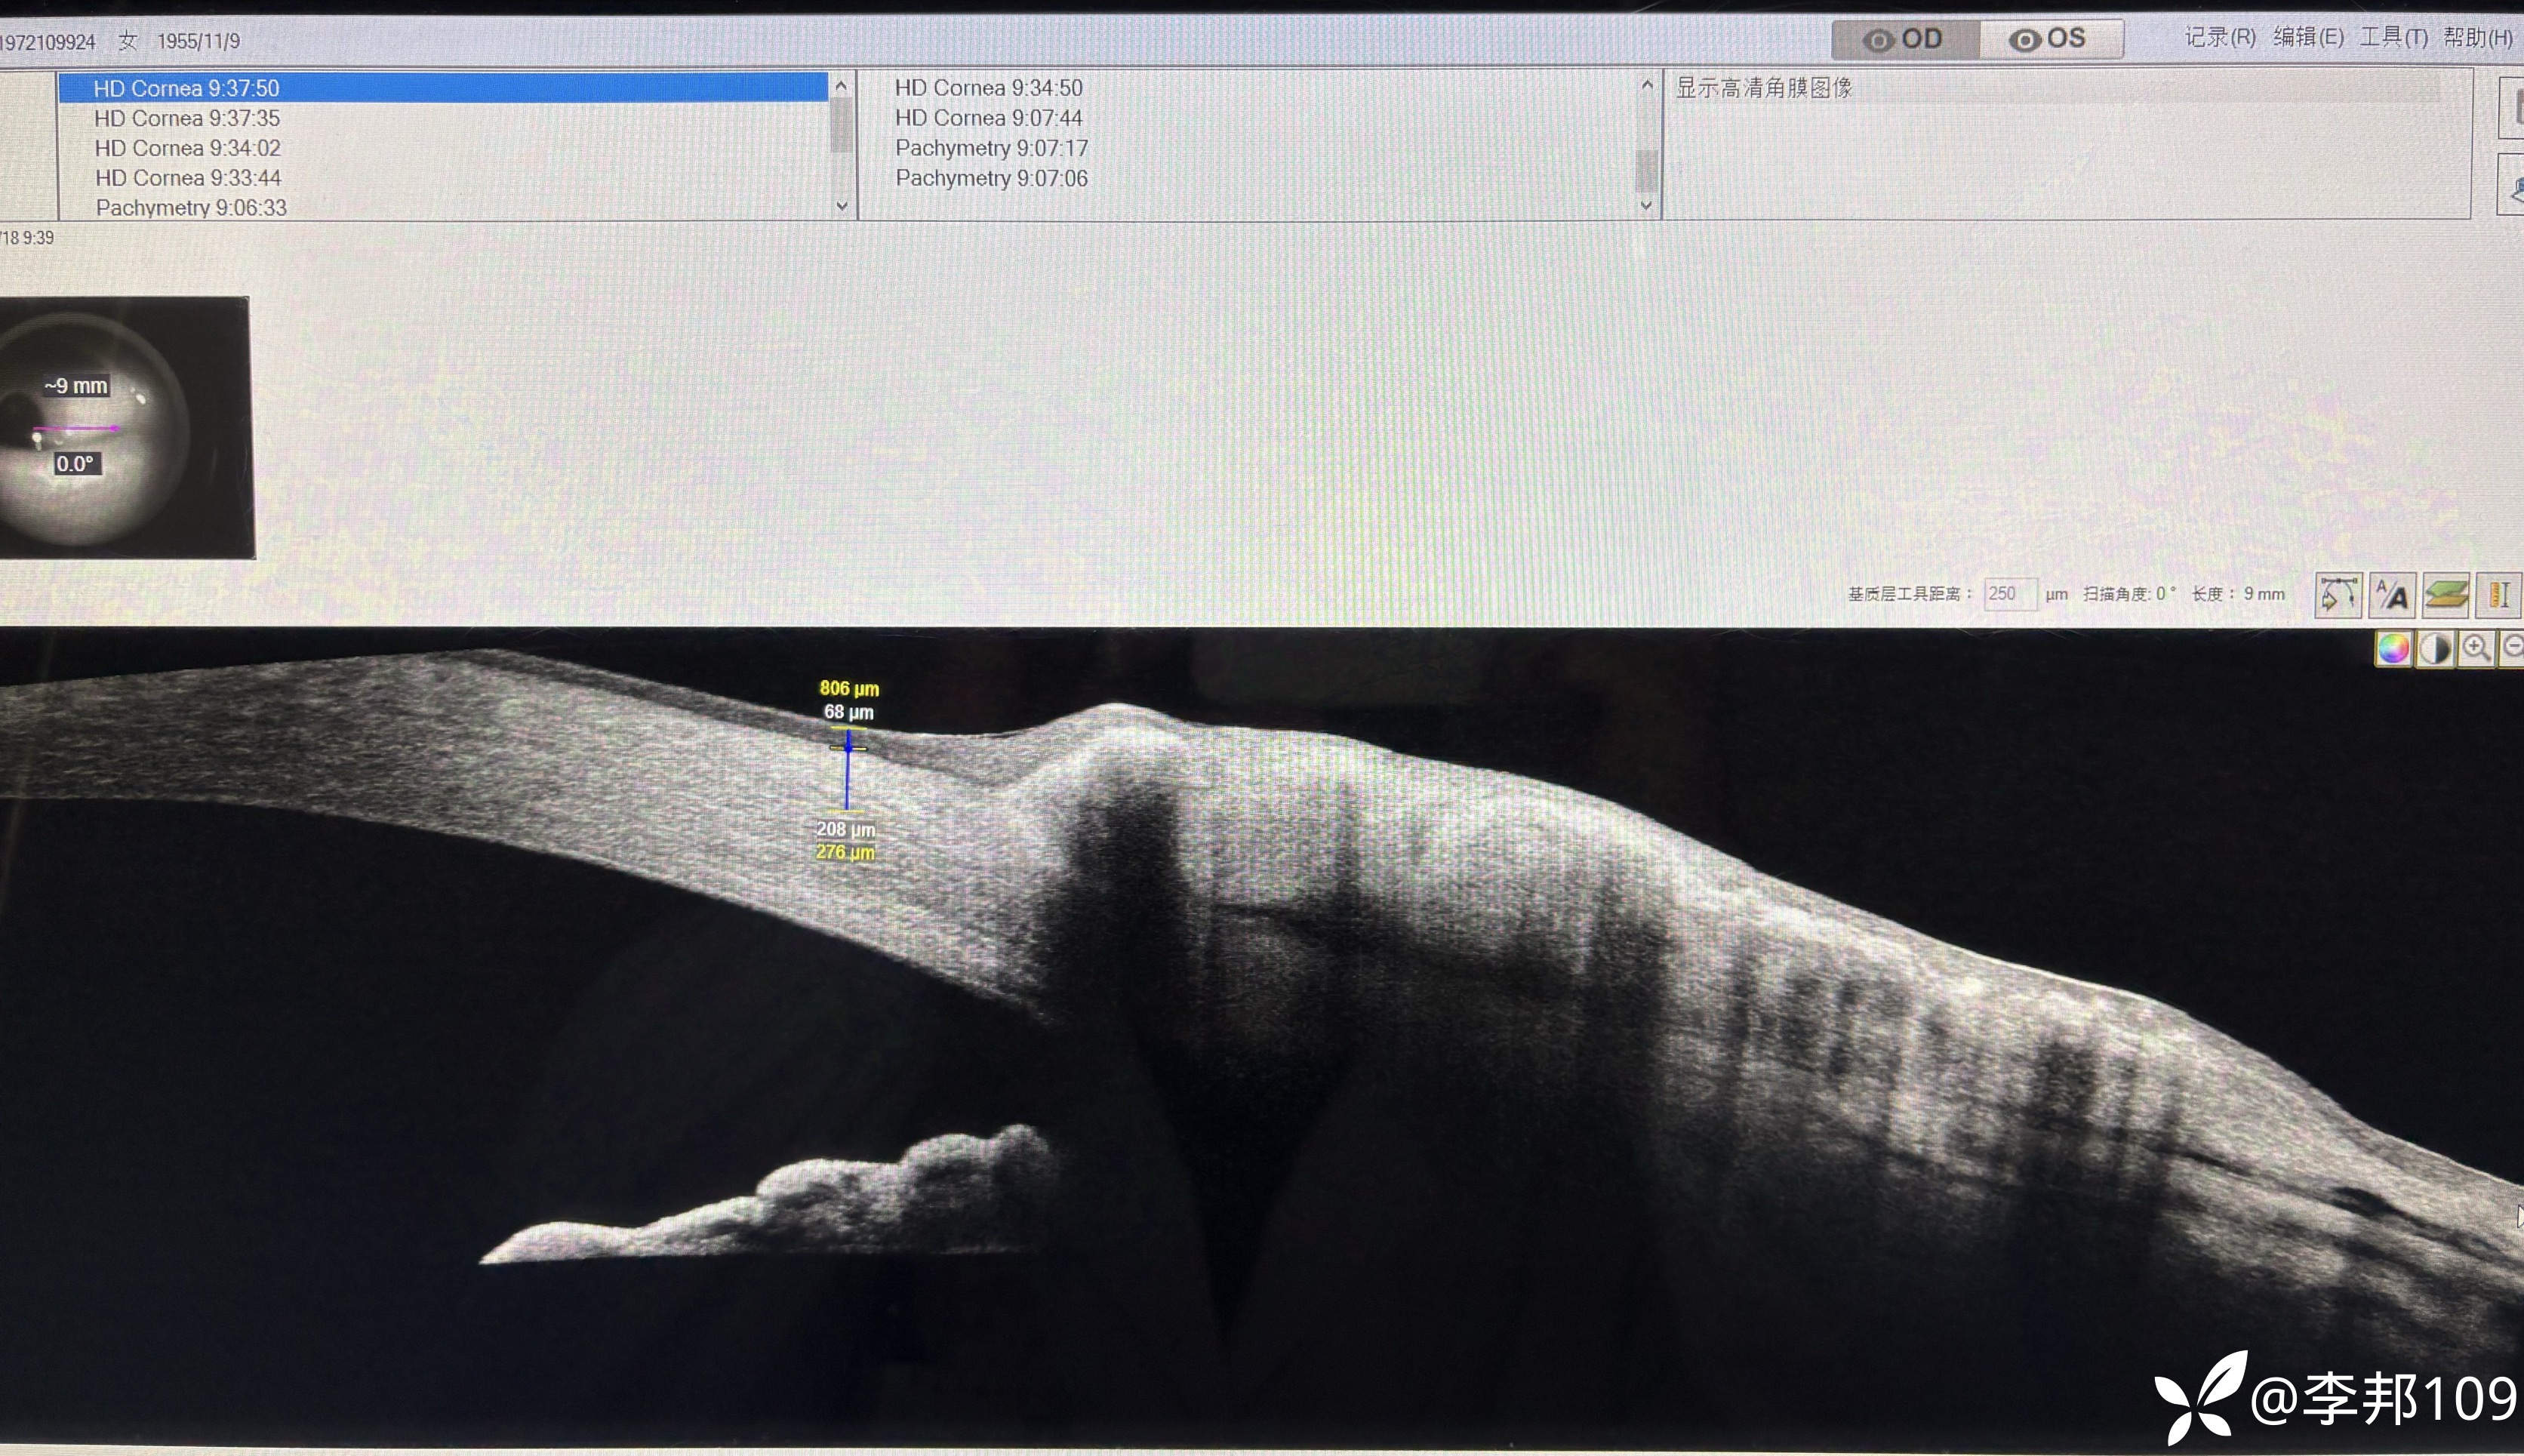

觉得不对劲,做了个AS-OCT,看看“”胬肉“”区的角膜上皮明显增厚

中央的上皮也增厚;颞侧上皮也增厚了